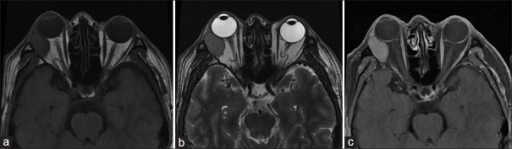

- CT: 눈물샘와 확대, 골 리모델링(매끄러운 확대)

- CT: 불규칙 골 파괴, 석회화 가능

- CT/MRI: 골 변화 패턴이 핵심 감별

- 골 리모델링(양성) vs 골 파괴(악성) ⭐⭐⭐